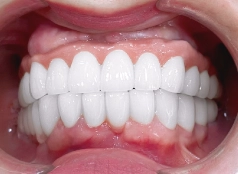

• Sử dụng răng sứ Cercon HT cao cấp, bền đẹp.

Kết thúc hành trình làm răng tại I-DENT, chị Khánh đã sở hữu cho mình một hàm răng trắng sáng, đều đẹp tự nhiên và giúp chị tự tin nở nụ cười rạng ngời khi giao tiếp với mọi người xung quanh!